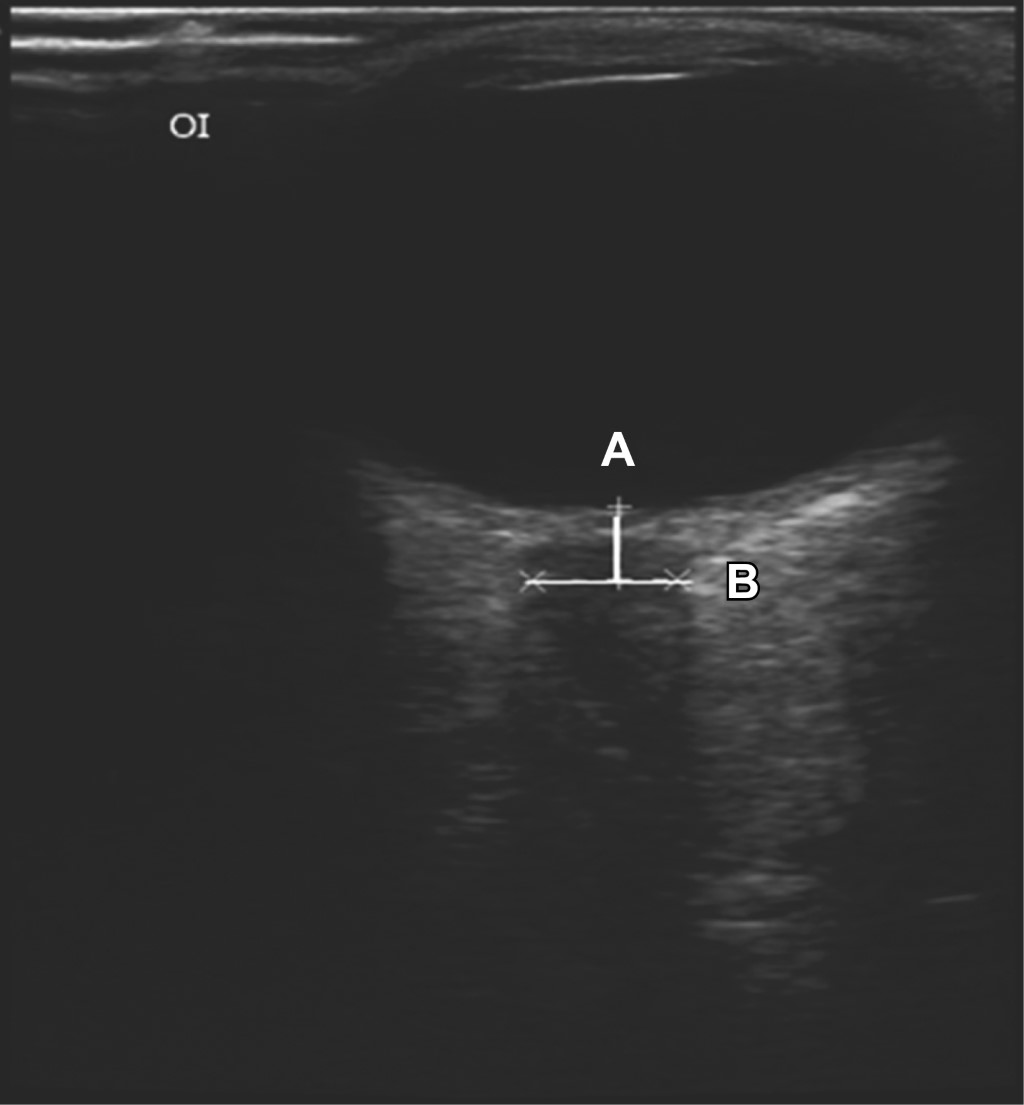

El nervio óptico aparece como una estructura hipoecogénica detrás de la retina y del disco óptico, lo que proporciona un hito anatómico para el examen con ultrasonido. La estructura hiperecogénica alrededor del nervio óptico representa el espacio subaracnoideo que está bordeado por la duramadre hipoecoica.28 Se deben realizar dos trazos: un primer vector vertical (A) desde la retina hasta la vaina que mida 3 mm y un segundo vector horizontal (B), perpendicular a éste pasando justo donde terminan los 3 mm, midiendo la totalidad del diámetro de la vaina que se observa hipoecoico como se muestra en la Figura 1.